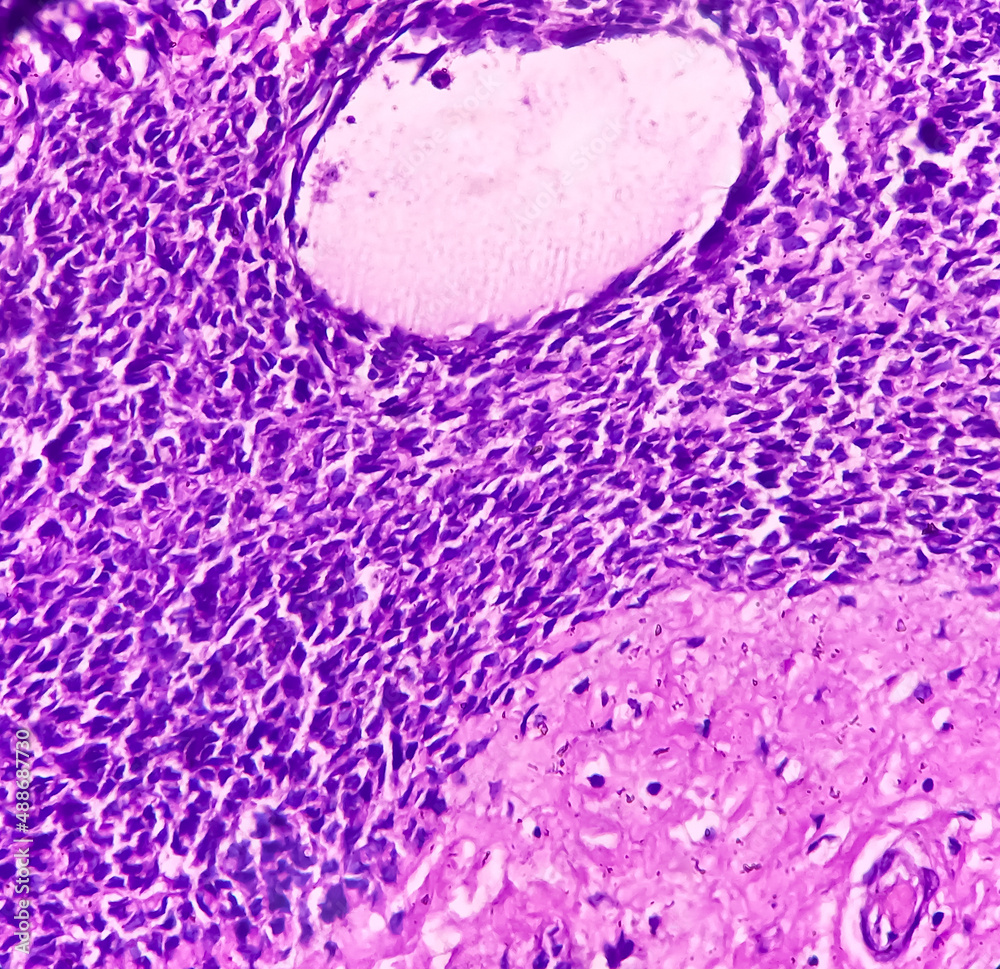

Scapula cancer Synovial monophasic, show malignant neoplasm Spindle Cell Neoplasm Sarcoma It can occur anywhere throughout the body, but it most commonly. Spindle cell sarcoma is a type of undifferentiated sarcoma. Spindle cell sarcomas of the bone are often found in the arms, legs. Spindle cell sarcoma is an extremely rare bone cancer. A spindle cell sarcoma is a soft tissue tumor that originates in a bone. Due to its rarity,. Spindle Cell Neoplasm Sarcoma.

Scapula cancer Synovial monophasic, show malignant neoplasm Spindle Cell Neoplasm Sarcoma Spindle cell sarcoma is a type of undifferentiated sarcoma. Spindle cell sarcoma is an extremely rare bone cancer. It can occur anywhere throughout the body, but it most commonly. Due to its rarity, only a few cases. Spindle cell sarcomas of the bone are often found in the arms, legs. A spindle cell sarcoma is a soft tissue tumor that. Spindle Cell Neoplasm Sarcoma.